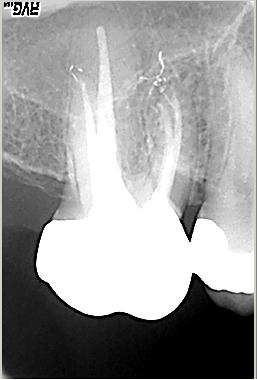

Röntgenologischer Ausgangsbefund im Febr. 2003 mit caries profunda, starken Krümmungen sowohl der mesiobuccalen wie auch der distobuccalen Wurzeln

Zustand unmittelbar vor Behandlungsbeginn im Juni 2003. Die Fraktur des distalen Zahnanteils hat die Patientin jetzt zur Einwilligung in die Behandlung motiviert. Auffällig ist in dieser Projektion die besonders starke Krümmung der mb Wurzel sowie die knochennahe Defektlage distal. Es erfolgte zunächst die Kariesentfernung gefolgt von einer chirurgischen Kronenverlängerung zur Herstellung der biologischen Breite sowie Ermöglichung des sog. Ferrule-Effektes. Danach wurde der Zahn adhäsiv aufgebaut. Erst jetzt wurde mit der eigentlichen WKB begonnen